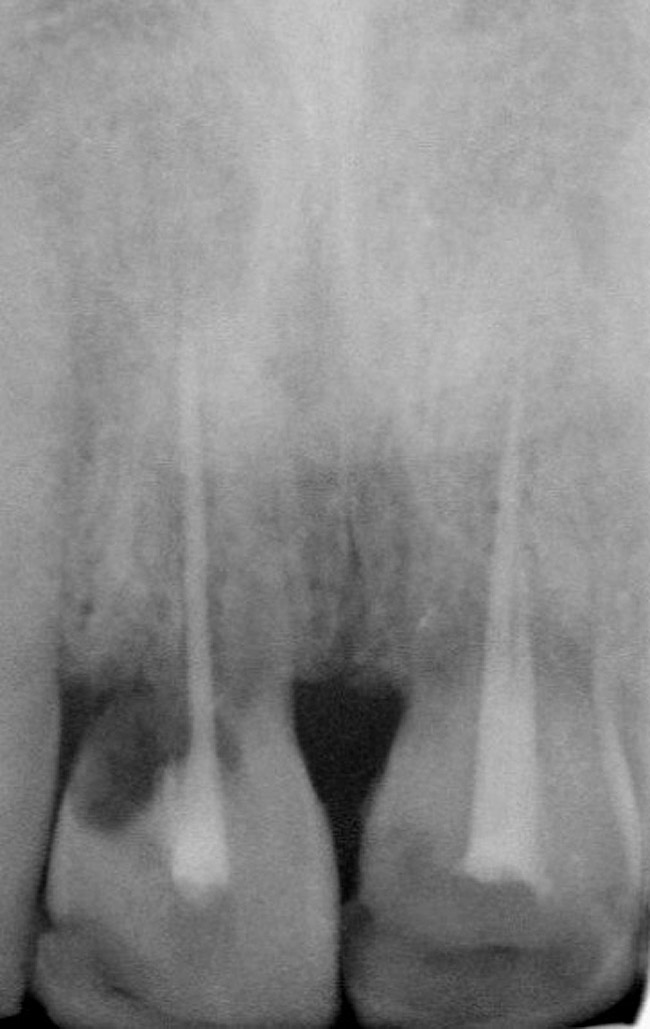

Figure 10   Periapical radiograph at the time of provisionalization. Note the wide peak of bone between implants Nos. 8 and 9.

Figure 10